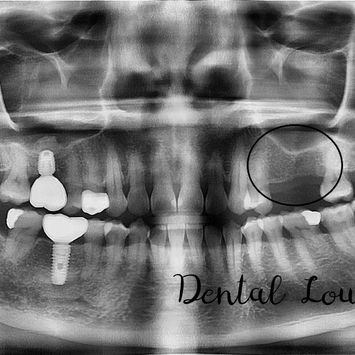

Implant Placement Surgery at #25 and #26

Missing upper left premolar and molar (#25 & #26) requiring implant-supported replacement.

Edentulous spaces at #25 and #26

Adequate ridge volume with need for ridge expansion

Sinus proximity requiring internal sinus lift

Pre-operative CBCT confirmed suitable anatomy for implant placement with augmentation